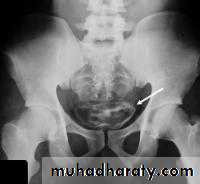

• Bladder calcification

• The most frequent cause of calcification is calculi ( large and laminated). Calcification in the wall is rare and usually due to schistosomiasis or bladder tumor.• Urinary bladder infection

• Tuberculosis: it is always associated with renal TB. It produce irregular wall thickening and decrease in bladder capacity due to fibrosis (thick contracted bladder). Calcifications is present in 10% of cases and could be seen on plain film and CT

Schistosomiasis: US may be normal at early stage, latter will show wall thickening(up to 1 cm or more) and multiple polypoidal lesions. Latter on calcification may develop which appear on plain film in 50% of cases as egg shell or linear calcification in the bladder wall and lower ureters. In contrast to TB, the bladder capacity and contractility is well preserved. The condition predispose to squamous cell carcinoma due to epithelial metaplasia.